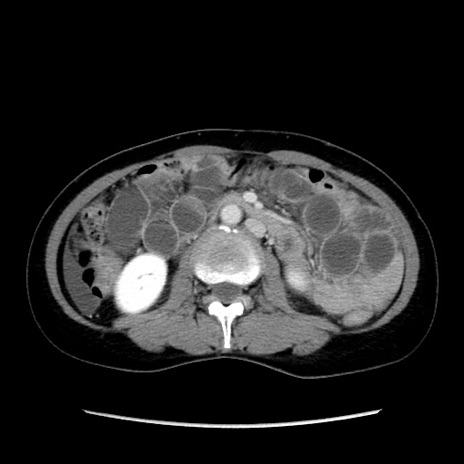

矢状断像